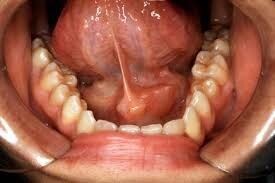

Bony Growth – A bony, round, hard bump on the gums is known as a dental torus (or tori plural). It’s a bony protrusion that grows on top of existing bone. The bumps are usually smooth and covered completely in gum tissue.

The different types of dental tori are classified by their location. For example, a torus mandibularis is located on the inside of the lower jaw on the side nearest the tongue. A torus palatinus is a protrusion from the roof of the mouth, or palate.

Dental tori don’t usually interfere with function or cause pain. Rarely, a tori will continue growing and become irritated or get in the way of dentures. In these cases, it may need to be removed.

There isn’t a known cause of bony growths on the gums but some experts think bruxism, genetic factors, diet and/or stress on the jaw from a bad bite may be the cause.